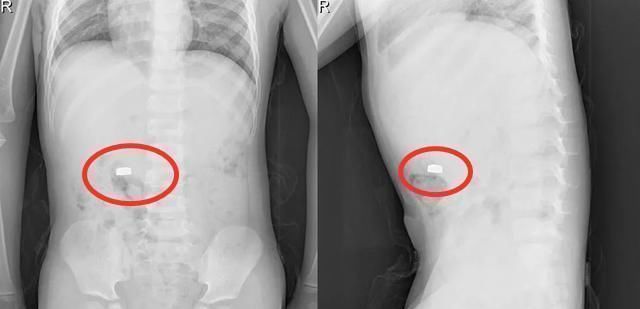

小宝开心地指了指自己的肚子,“我把它吃了!”小宝还想向妈妈炫耀自己的成果,可李姐已经傻了眼,反应过来后,立刻抱着孩子冲进医院。

所幸孩子最终并无大碍,但父母也应当提高安全意识,家里的这些小东西一定要提醒孩子远离它们。